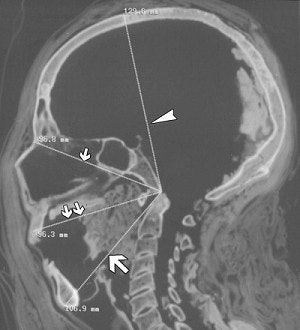

| Male mummy of unknown provenance, dating from New Kingdom to Third Intermediate period. Midline sagittal reconstruction of CT image with anthropometric measurements of skull marked shows basion-bregma height (129.6 mm) (arrowhead); nasion-basion diameter (96.8 mm) (small single arrow); basion-prostion diameter (96.3 mm) (small double arrows); and basion-gnathion diameter (106.9 mm) (large arrow). Cesarani F, Martina MC, Ferraris A, Grilletto R, Boano R, Marochetti EF, Donadoni AM and Gandini G. "Whole-Body Three-Dimensional Multidetector CT of 13 Egyptian Human Mummies," (AJR 2003, Vol. 180, pp. 597-606). |